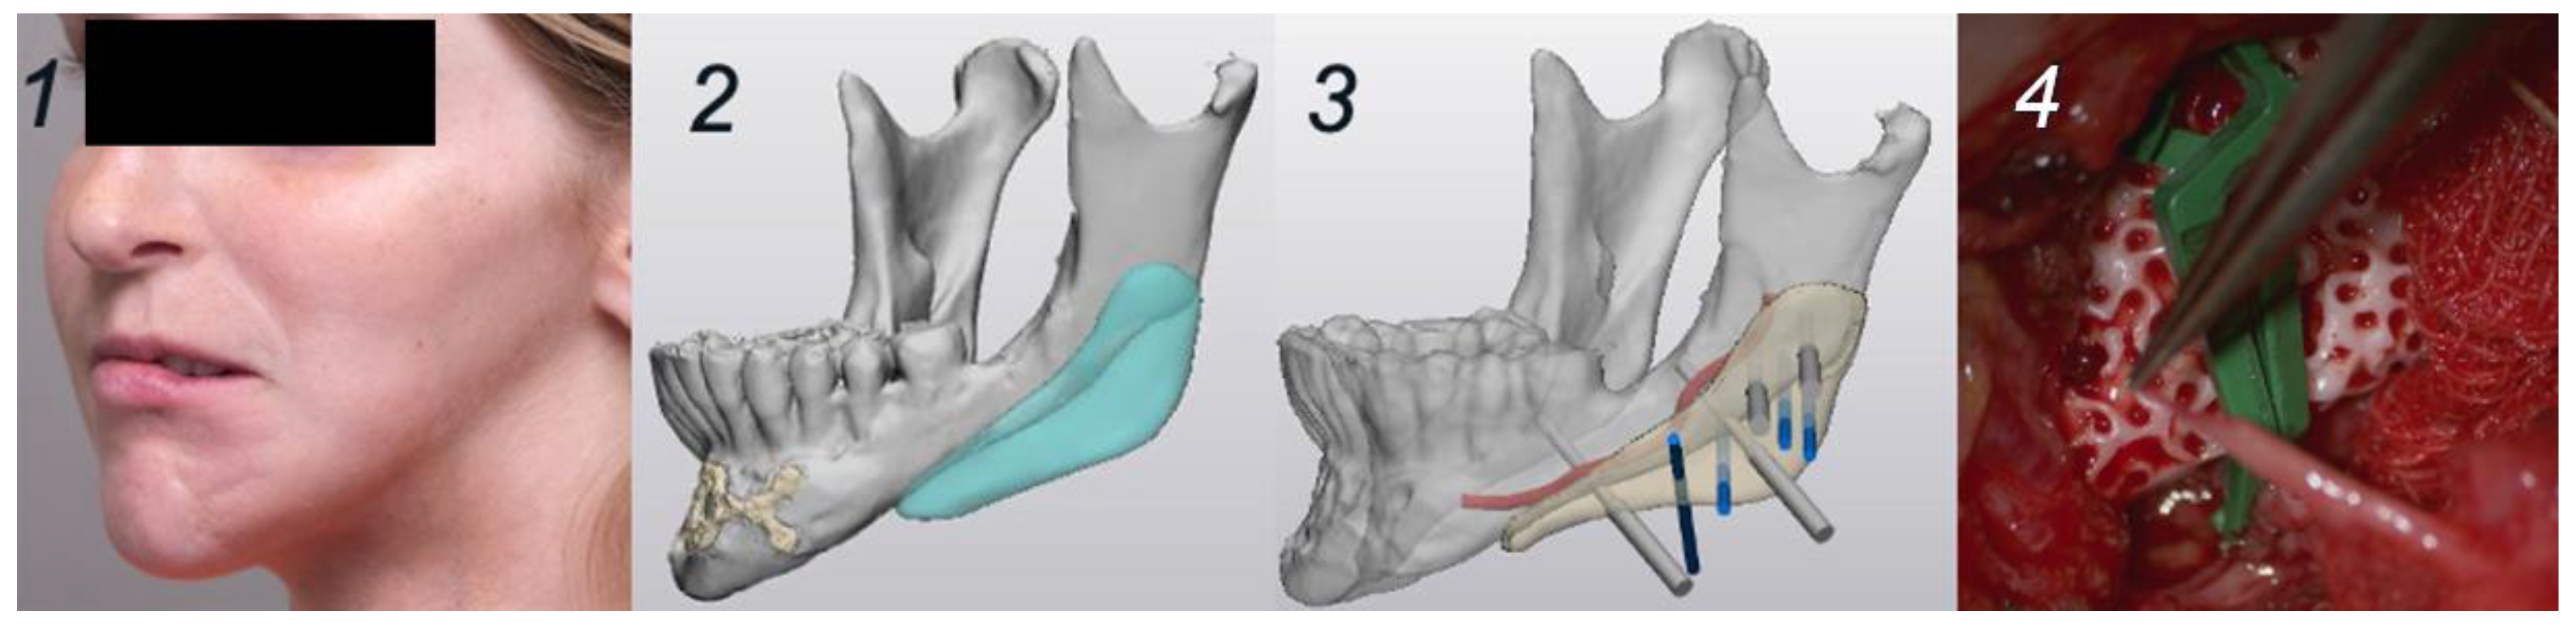

Figure 3.

Planning and surgery, case 2. (1): Clinical situation pre-surgery, 45° left. (2): Digital design of the PSI. (3): Digital design of the fixation screws in relation to the alveolar nerve. (4). PSI placement and fixation.

A 19-year-old woman was planned for reconstructive surgery of the left mandibular angle as part of a multistage treatment plan for left hemifacial asymmetry secondary to Parry–Romberg syndrome. The HA bioceramic PSI and corresponding cutting guide were virtually planned in Mimics and Proplan CMF™ (Materialise, Leuven, Belgium) mirroring the contralateral side. Based on the 3D CT images (0.6 mm slices), the screw holes were positioned in favorable relation with the alveolar nerve (Figure 3). The manufacturing process was equivalent to the first case. Lipofilling with peri-umbilical fat and a Superficial Circumflex Iliac Artery Perforator (SCIAP) flap were planned for soft tissue reconstruction. The prepared surgery was initiated with an extra-oral approach incising in the peri-angular region on the left side, dissecting and containing important nervous structures such as the marginal branch of the facial nerve. The 3D-printed cutting guide was inserted to drill the screw holes. The PSI was evaluated in the planned position before fixation. After insertion and fixation of the implant using 2 screws, the SCIAP-flap was harvested and anastomosed on the facial artery and vein (Figure 3). Surgery was completed with lipofilling of the left upper lip with harvested free abdominal fat.

In the second clinical case, the postoperative period showed beneficial healing of the PSI and donor site of the SCIAP flap. The aesthetic and functional results were satisfactory (Figure 5), although a discrete step was palpable, representing the transition of the mandible and the implant. No neurological deficits of the facial or trigeminal nerves were observed. CT imaging 2.5 months postoperatively showed a good position of the implant and absence of signs of infection around the screws (Figure 5).

Figure 5.

Clinical and radiological (CBCT) situation preoperatively and after 2.5 months, case 2. (1): Clinical situation pre-surgery—frontal plane. (2): Clinical situation 2.5 months post-surgery. (3): Radiological situation pre-surgery. (4): Radiological situation 2.5 months post-surgery.